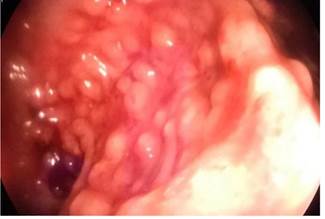

Se trata de un paciente de 15 años de edad, sin antecedentes patológicos previos, que fue remitido a nuestro hospital por hematoquecia. Sus antecedentes familiares son variados: madre diabética tipo 2, tía materna con esclerodermia, tía materna con amiloidosis y bisabuela con cáncer gástrico. Refirió el inicio de enfermedad a los 7 años de edad con cuadro clínico de hematoquecia y dolor abdominal de leve intensidad que mejoraba después de la defecación. En 2011 se realizó una colonoscopía con hallazgos de lesiones sobreelevadas pseudopolipoideas de 3 a 4 milímetros en el colon sigmoide y el recto con una biopsia que reportó malacoplaquia. Recibió tratamiento con ciprofloxacino 500 mg vía oral por 14 días, que mejoró su sintomatología. En 2016 se realizó otra colonoscopia por presentar proctorragia y leve dolor abdominal. Nuevamente se describieron formaciones nodulares pseudopolipoideas en el sigmoides y el recto (Figura 1), con una biopsia que reportó pólipos inflamatorios con focos de agudización, numerosos histiocitos y cambios reactivos del epitelio. En este evento, recibió tratamiento con ciprofloxacino 500 mg vía oral cada 12 horas por 14 días y presentó mejoría de la sintomatología. En julio de 2018, se realizó otra colonoscopia que informó lesiones pseudopolipoideas de distribución irregular con mucosa colónica normal, áreas planas de aspecto nacarado de bordes irregulares (Figura 2), con una biopsia que reportó pólipos inflamatorios, colitis crónica acentuada con tinción de ácido periódico Schiff (PAS), sin encontrar cuerpos de Michaelis-Gutmann.

Figura 1 Videocolonoscopia en la que se observa la mucosa del colon sigmoide y recto con formaciones nodulares pseudopolipoideas.

La videocolonoscopia reveló a nivel del colon sigmoide y recto múltiples formaciones pseudopolipoideas sésiles, blandas, ulceradas y hemorrágicas, que medían de 5 a 15 mm de diámetro (Figuras 5 y 6).

Figura 5 La mucosa del colon sigmoide mostró lesiones pseudopolipoideas pequeñas que se asemejan a una poliposis en la videocolonoscopia.

Figura 6 Videocolonoscopia a nivel de la mucosa del colon sigmoide y recto en la que se observaron múltiples formaciones pseudopolipoideas sésiles, blandas, ulceradas y hemorrágicas que midieron de 5 a 15 mm de diámetro.